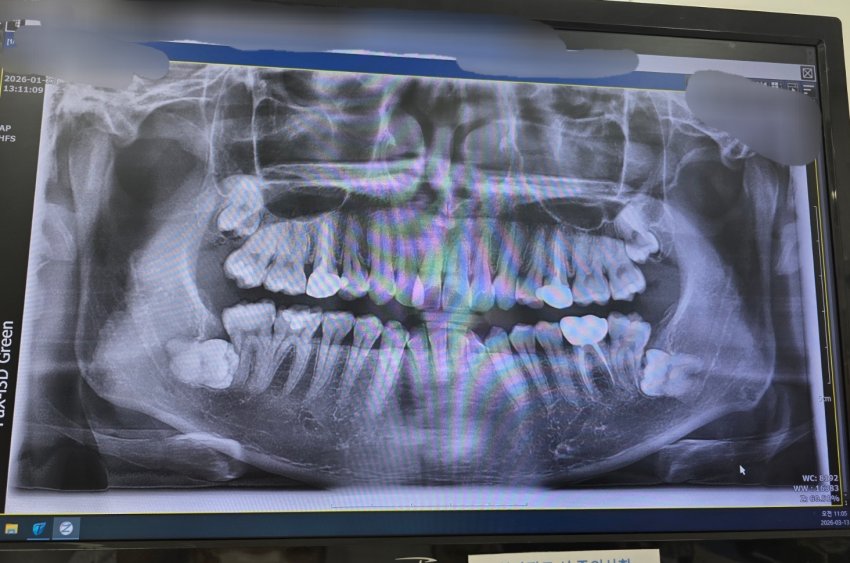

4.

HKhJHT

LIsBSt

위에는 별거 아닌거 같은데 아래 2개는 빡세보여서....